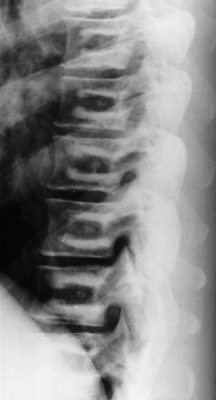

Single lateral lumbar spinal x-ray revealing increased sclerosis in the superior and inferior portions of the midbody of the vertebra. This is seen in vertebrae that have a small replica of the vertebral body inside the normal one, giving a bone-in-bone sign. It is produced by failure of osteoclastic activity causing abnormally dense bone that occurs intermittently producing zones of abnormal density alternating with relatively more normal bone. This is a characteristic finding seen in osteopetrosis.

Lateral thoracic spine - Click on the image for a larger version